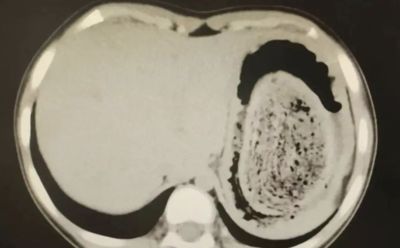

福建一名年僅10歲的女孩長期腹痛難耐,她忍痛3年、輾轉多家醫院未能找出病因,直到前往福建兒童醫院檢查時才揭曉真相。這名女孩胃裡塞滿成團頭髮,幾乎佔了胃容量的四分之三,導致「胃石」形成,引發持續性腹痛和缺鐵性貧血。醫師提醒,這種異常行為在醫學上稱為「異食癖」,多與心理問題相關,家長必須正視孩子的心理健康。 《詳全文...》